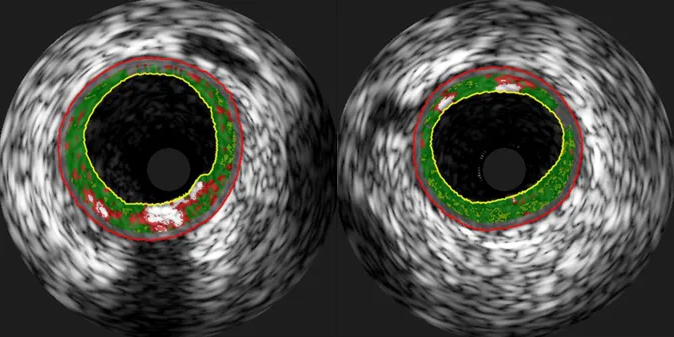

We have found four micro-RNA molecules that change levels after a period of exercise, and which are also associated with reduced plaque burden in the coronary arteries of heart patients. The results come from a study in which 31 patients either trained intensive intervals or with moderate intensity three days a week after they had opened narrow blood vessels in the heart. We examined their vessels with intravascular ultrasound both before and after the exercise period.

Micro-RNAs are tiny particles that regulate the activity of our genes. Many micro-RNA molecules are involved in various stages of the atherosclerosis process that clog blood vessels and lead to cardiovascular disease. In this study, we pre-defined 13 micro-RNA molecules that we examined further, based on results from previous studies.

After three months of training, the levels of micro-RNA-146a-5p had increased, while the levels of micro-RNA-15a-5p, 93-5p and 451a had decreased. All of these changes were also linked to a reduction in the total amount of plaque in the blood vessels of the patients. The study can not say anything about causation, but we can speculate that exercise leads to changes in micro-RNA that are beneficial in reducing coronary artery plaques in heart patients.

In addition, we found that the levels of six micro-RNA molecules were linked to a larger necrotic core. This plaque core consists of inflammatory cells and fat, and plaques with a lot of fat are more vulnerable to rupture that leads to heart attacks. However, changes in this necrotic core after an exercise period were not related to how micro-RNA levels changed during the same period.

Micro-RNAs are tiny molecules that regulate the activity of our genes. There are several thousand such micromolecules, and in our study we measured the levels of 160 different micro-RNAs in 47 patients with stable coronary artery disease. We also took ultrasound images of the inside of the patients' coronary arteries, and with the method of near-infrared spectroscopy we found the most fatty plaques.